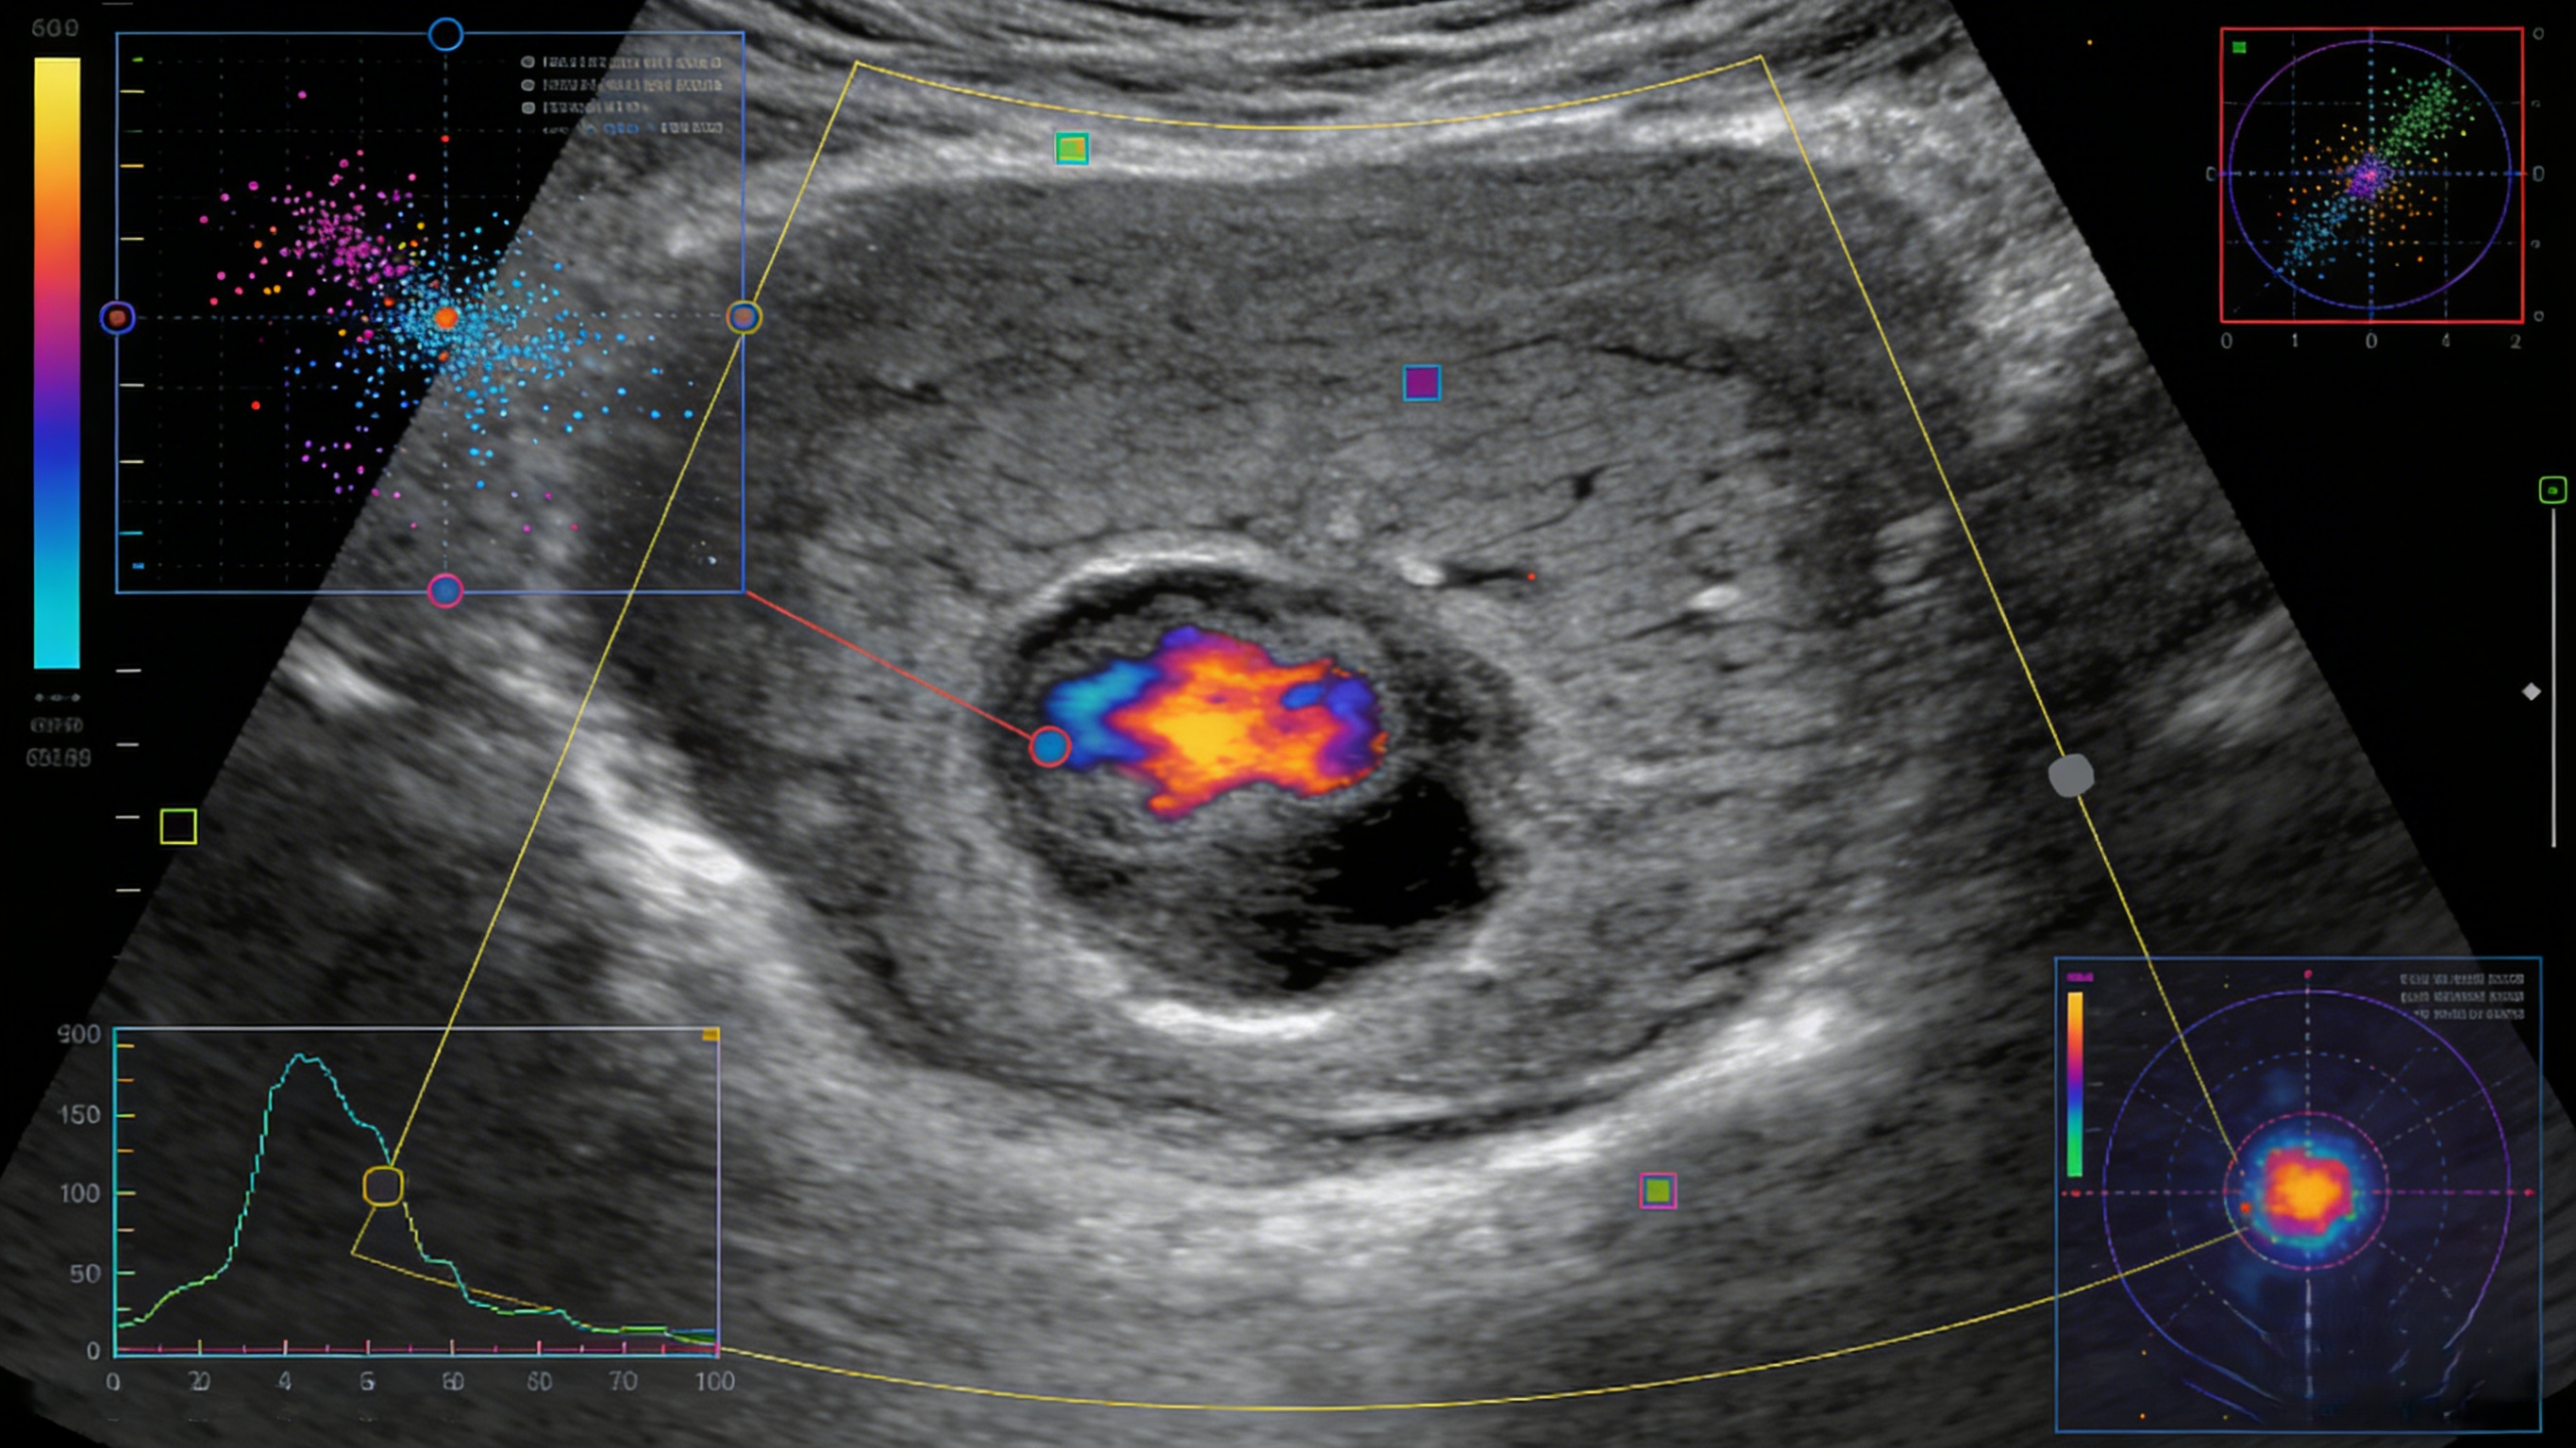

图源:CMT

封面图源:CMT